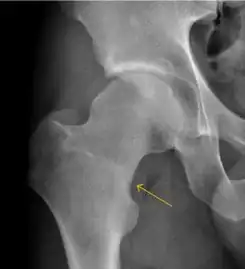

Stress femoral neck fracture in a young athlete barely visible in X-ray film as a sclerotic line (arrow)[1]

In this case, Tc 99 scintigraphy shows a band of uptake[1]

Furthermore, T1 (left) and DP fat saturated (right) weighted MR images showed the fracture line and a pattern of edema.[1]

MRI has been shown to have 100% sensitivity and specificity in prospective studies of occult hip fractures. These fractures were diagnosed by bone marrow edema and a low signal fracture line, mainly on T1 or T2 weighted images (Figure 10).[1]

Figure 10: